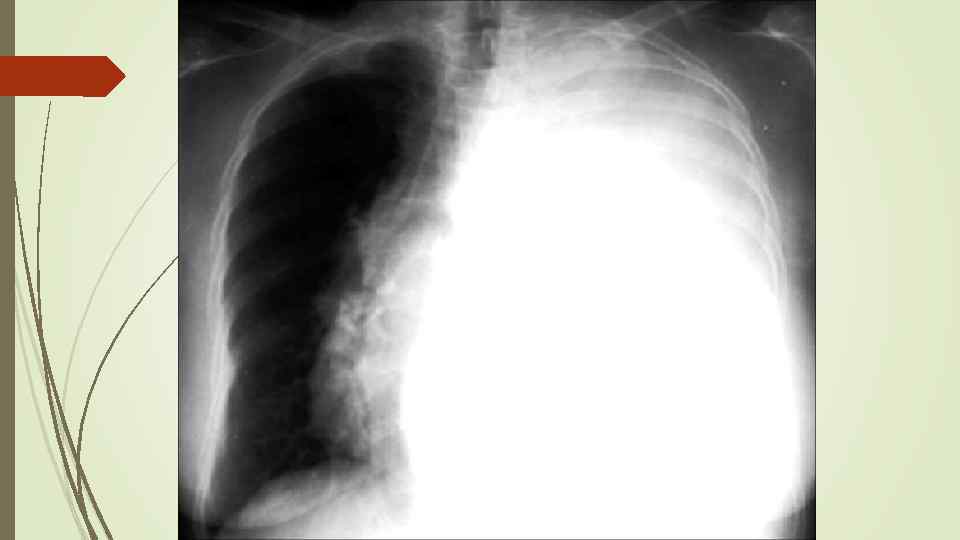

Плевральный выпот Скопление жидкости в плевральной полости (исключение гемоторакс, хилоторакс, пиоторакс) Транссудат Экссудат Плеврит

Плевральный выпот Скопление жидкости в плевральной полости (исключение гемоторакс, хилоторакс, пиоторакс) Транссудат Экссудат Плеврит

Осумкованные плевриты: а) пристеночные (паракостальные) осумкования, прилежащие широким основанием к поверхности ребер; б) верхушечные (апикальные) осумкования; в) диафрагмальные (базальные) осумкования, расположенные между основанием легкого и диафрагмой; г) междолевые (интерлобарные) осумкования, расположеные между долями легких; д) парамедиастинальные осумкования, расположенные в заворотах парамедиастинальной плевры.

Осумкованные плевриты: а) пристеночные (паракостальные) осумкования, прилежащие широким основанием к поверхности ребер; б) верхушечные (апикальные) осумкования; в) диафрагмальные (базальные) осумкования, расположенные между основанием легкого и диафрагмой; г) междолевые (интерлобарные) осумкования, расположеные между долями легких; д) парамедиастинальные осумкования, расположенные в заворотах парамедиастинальной плевры.

Гидропневмоторакс имеет такие же причины возникновения и рентгенологические проявления, как и пневмоторакс, но в плевральной полости помимо воздуха находится жидкость. Рентгенологически помимо общих признаков с пневмотораксом появляются дополнительные: - затемнение высокой интенсивности и однородной структуры, нижняя граница которого сливается с диафрагмой, а верхняя при вертикальном положении образует горизонтальный уровень; - средостение резко смещено в противоположную сторону.

Гидропневмоторакс имеет такие же причины возникновения и рентгенологические проявления, как и пневмоторакс, но в плевральной полости помимо воздуха находится жидкость. Рентгенологически помимо общих признаков с пневмотораксом появляются дополнительные: - затемнение высокой интенсивности и однородной структуры, нижняя граница которого сливается с диафрагмой, а верхняя при вертикальном положении образует горизонтальный уровень; - средостение резко смещено в противоположную сторону.